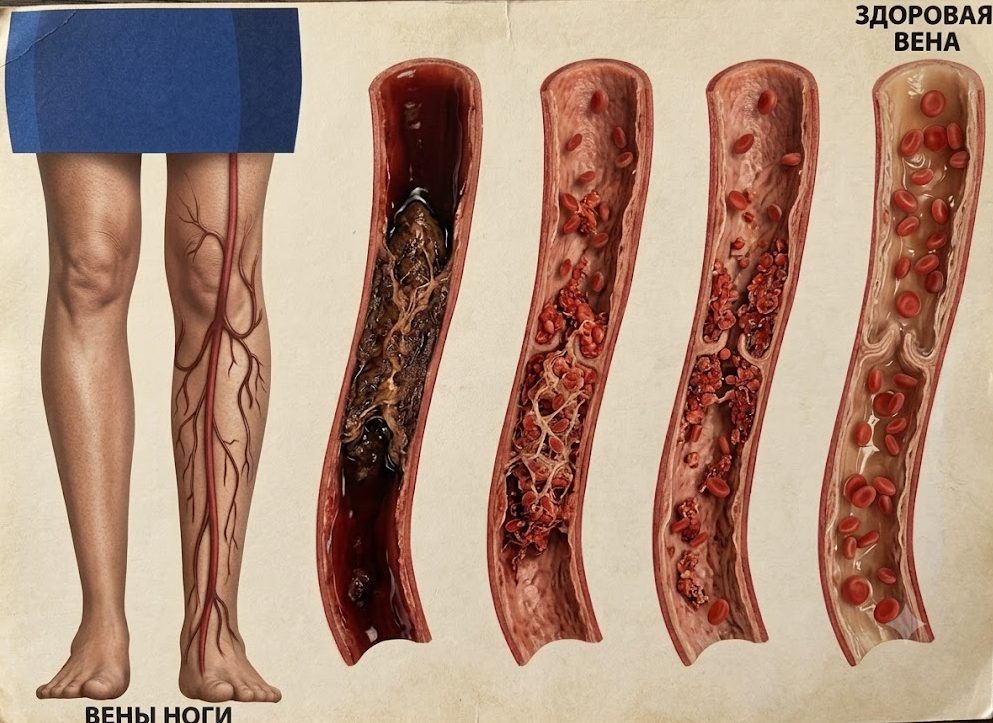

- Удаление сосудистых звездочек на ногах лазером

- ЭХО-склеротерапия вен

- Комбинированная флебэктомия

- Минифлебэктомия

- Флебэктомия вен нижних конечностей

- Пенная склеротерапия вен

- Эндовазальная лазерная коагуляция вен (ЭВЛК)

- Склеротерапия вен

- Флебология